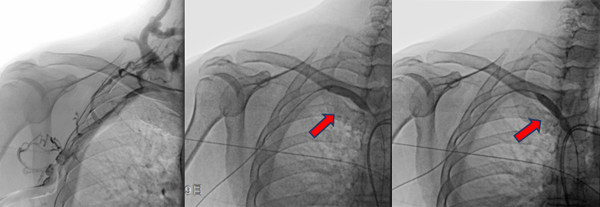

病变明确了,张主任当机立断,立即进行介入手术。张东亮主任医师与付晨主治医师在新建成的新龙泽院区介入手术中心进行了局麻下经皮穿刺血管内介入治疗。张主任凭借丰富的经验、娴熟的手法很快将超滑导丝通过病变部位,10mm高压球囊将狭窄部位扩张至无回弹,再次造影确认,心细的张主任又发现了新的端倪——近心端静脉还有一处狭窄!此前这一病变在CTA+CTV结果中并没有发现,张主任毫不犹豫,球囊再前进50mm、打压扩张,再次造影复测,血流通畅、侧支循环和返流消失。

狭窄的两处病变静脉在球囊的逐渐加压得以重新开通